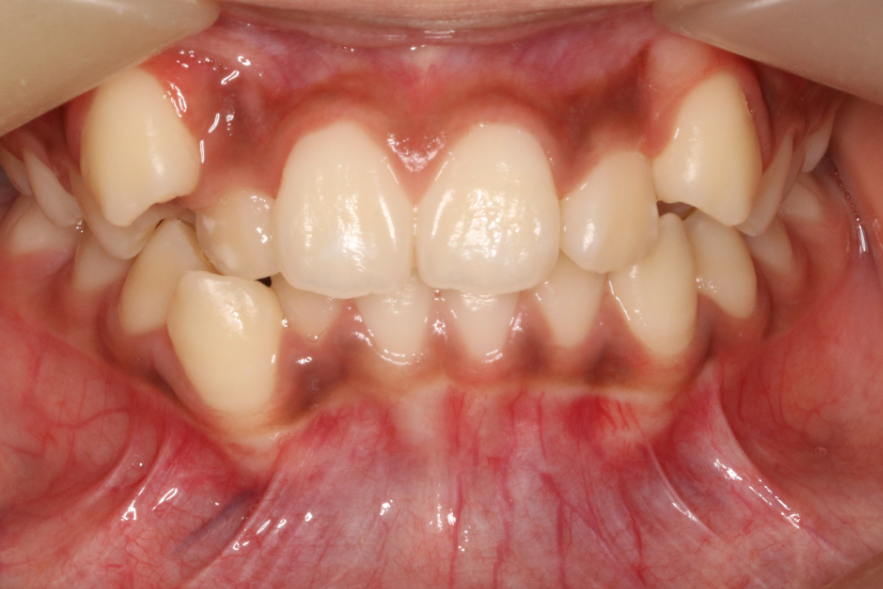

治疗前                        治疗后

无托槽隐形矫治技术

儿童错合畸形早期矫治是阻断影响儿童颌骨、牙齿正常发育的因素,促进颌面部正常发育,降低II期矫正的难度,减少II期矫正的时间,甚至不需要II期矫正。让孩子早期获得自信,绽放灿烂笑容。

术前→术后